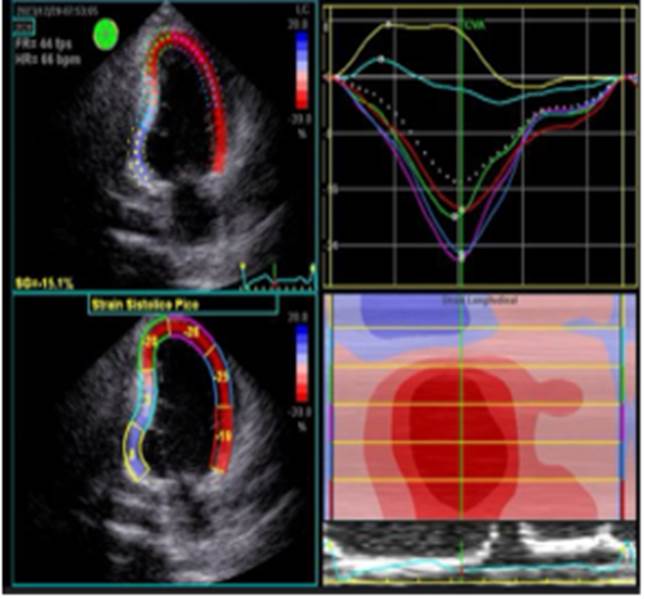

Posterior al alta se realizan controles por consulta externa en nuestro hospital, paciente con mejoría clínica marcada que se evidencia en la tolerancia al decúbito dorsal presentando además cambios beneficiosos en su clase funcional de la NYHA I/IV, en su FEVI al doble en comparación a la FEVI inicial, se mantiene medicación ambulatoria para insuficiencia cardiaca. El control ecocardiográfico 3 meses posteriores al evento muestra trastornos de motilidad en cara inferior con un strain sistólico pico GLPS: -13.5%, mejoría de la FEVI del 44% ilustación 8 y Fig 9, ya no se visualiza Pseudo Aneurisma del septum interventricular persistiendo una pequeña alteración morfológica de la pared inferior del VI que se confirma con la deformidad pico longitudinal disminuida a predominio de la pared inferior basal.

Ilustración 8 Strain sistólico

Fuente: Hospital de Especialidades Guayaquil “Doctor Abel Gilbert Pontón”.

Autor: Dra. María Sánchez Sánchez.

Ilustración 9 Ojo de buey

Ecocardiografía posterior a cirugía donde evidencia área discinética como secuela de reparación quirúrgica Fig 8 y 9.